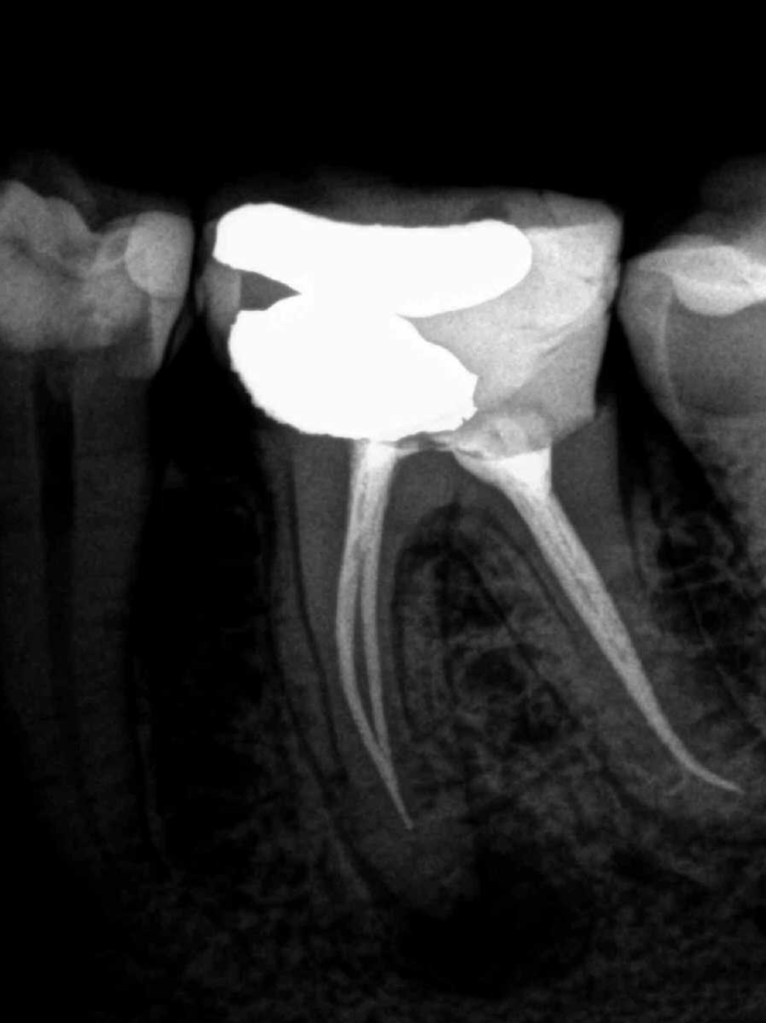

Retratamiento Molar Superior

Retratamiento Primer Molar Superior